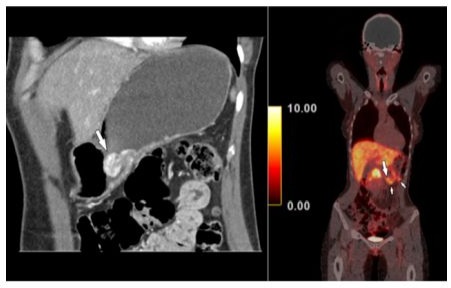

Hence, a radiological assessment was requested. Contrastenhanced hydro-multidetector computed tomography (MDCT) of the stomach after oral administration of 1500 ml of water showed a hypervascular polypoid mass in the gastric body (Figure 1) as well as two hypervascular lymph nodes close to the greater curvature. Findings were corroborated by somatostatin receptor analogue (68Ga DOTANOC) PET/CT, which demonstrated not only the hypermetabolic gastric tumor, but also two lymph nodes adjacent to the stomach with an SUVmax of 6.6 (Figure 1). MDCT and PET/CT features were consistent with the presence of a NET, without demonstrating the morphology of another tumor entity. Radiologically, there were no signs of transmural infiltration of the gastric wall.